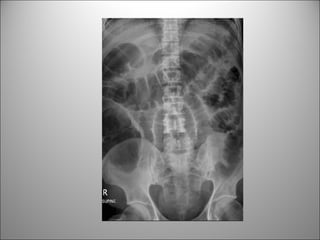

PATRÓN DE GAS INTESTINAL

• Contraste natural

• Puedo diferenciar entre Int. delgado y cólon?

– Si, principalmente si hay distensión

Dato clave:

REGLA DEL 3/6/9

3 cm Int. Delgado

6 cm Colon

9 cm Ciego

Apariencia normal de cada sección:

EL COLON

• Taenia coli + musc. Circulares  haustras

•Posición periférica

• Transverso y

sigmoides posición

variable

• Haustras

• Heces